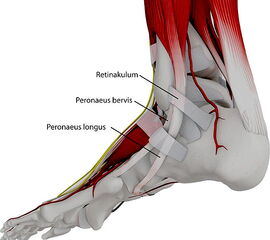

Die Peroneus brevis und die Peroneus longus Sehne verlaufen normalerweise hinter der Fibula (Abbildung 1). Neben der Gleitrinne an der Fibularückfläche sorgt das Retinaculum peroneale und das Retinaculum extensorum für eine weitere Stabilisierung. Bei der Peronealsehnenluxation oder –Instabilität können verschiedene Formen unterschieden werden (Abbildung 2):

Etwa ein Drittel der Sehnenluxationen entsteht jedoch idiopathisch ohne adäquates Trauma. Als Ursache wird hier neben einer Schwäche des Retinaculums eine unzureichende Tiefe der Sehnenrinne an der hinteren Gelenkfläche der Fibulaspitze mit flacher Randleiste angenommen 567.